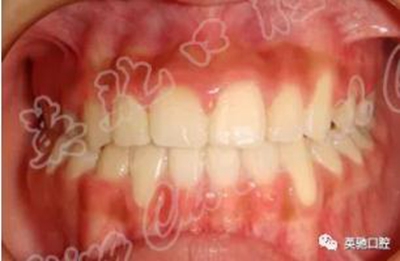

患者進(jìn)行前牽引5個月。后期繼續(xù)排齊整平牙列,精細(xì)調(diào)整咬合關(guān)系。療程1年半。因為右上尖牙萌出不足,所以療程稍長,否則療程會明顯縮短。隨訪2年以上療效穩(wěn)定。